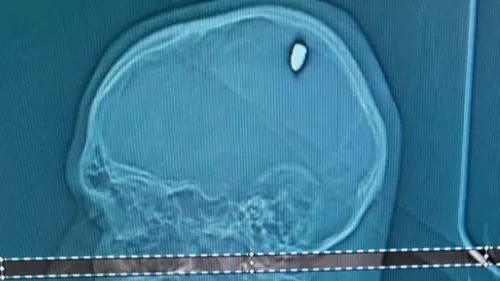

Il croyait avoir trop bu : un étudiant découvre une balle de 9mm...

Après quatre jours de gueule de bois, un étudiant brésilien découvre qu'une balle de 9mm était en fait venue se loger dans son crâne le soir du nouvel-An.